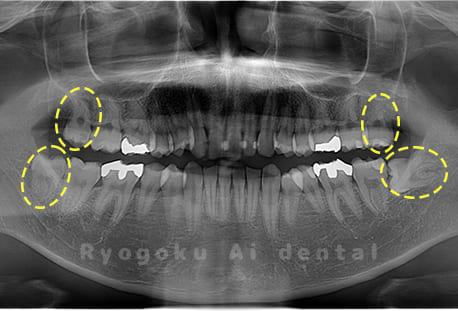

Case04

-

- 原因

- 上顎の親知らず、下顎の水平埋伏の親知らず

- 治療内容

- 上顎の親知らず、下顎の水平埋伏の親知らずを抜歯したケースです。

<リスク・副作用>